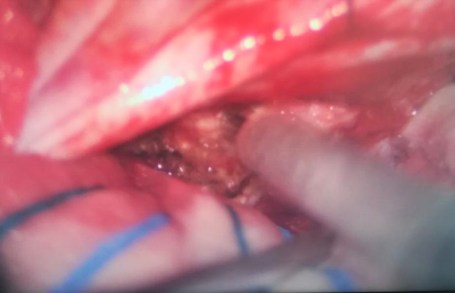

La operación se llevó a cabo en la Unidad Médica de Alta Especialidad No. 14 del Centro Médico Nacional «Adolfo Ruiz Cortines» del IMSS, en el puerto de Veracruz, y en ella se utilizó una avanzada técnica que requirió de un aspirador ultrasónico que fragmentó, emulsificó y aspiró el tumor cerebral, sin dañar otros tejidos, vasos y nervios, en este caso, del cerebro.

Durante el procedimiento se aplicó a la paciente pequeñas descargas eléctricas en el cerebro, que funcionaron como estímulos para evaluar la respuesta motora, delimitar específicamente el tumor y evitar posibles daños a partes sanas del cerebro al momento de retirar el tejido anormal.

Al ser valorada y tratada por el servicio de Neurología de la UMAE, la tomografía reveló una tumoración de tres por tres centímetros: «Se encontraba alojado en la región temporal del lado izquierdo y causaba mucha irritación en la corteza del cerebro, dicho lugar es donde podemos encontrar la región del habla y la zona primaria de la audición, además de ser un área generadora de epilepsia», agregó.

«Una de las complicaciones con las que nos encontramos fue que el tumor era nutrido por una vena profunda muy importante, el problema de daño severo era muy alto, ya que se encontraba cerca de una región llamada tallo cerebral y causaba demasiada inflamación», comentó el especialista.